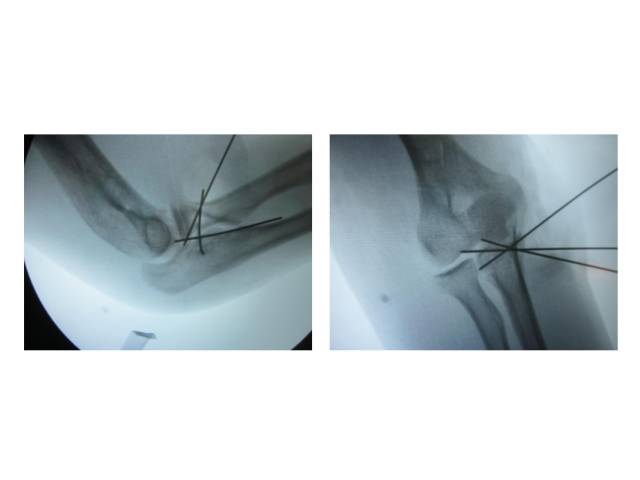

02

手术入路